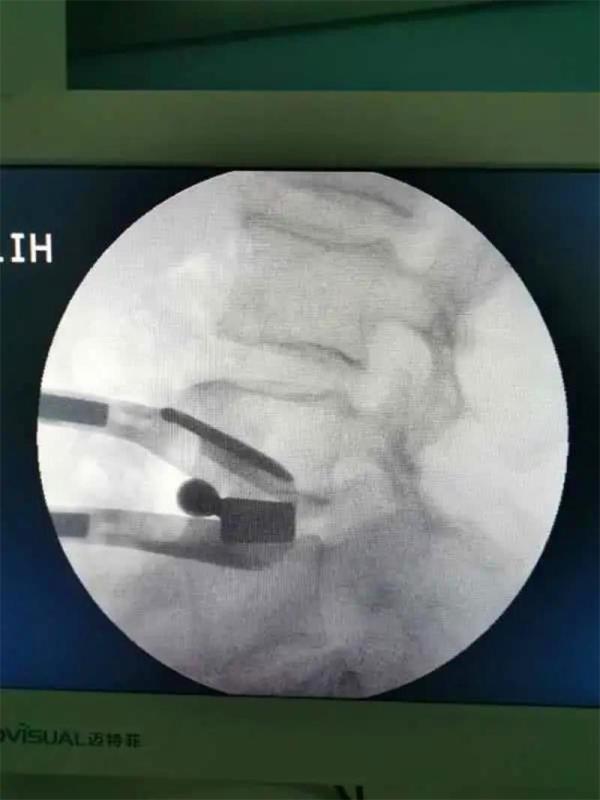

昆明市中医医院骨伤科关上病区在江苏省中医医院(南京中医药大学附属医院)骨伤科主任陈刚的指导下,5月中旬,顺利完成2例腰椎微创新技术——腰椎斜向椎体间融合术(OLIF)。并通过网络会议形式开展了“OLIF的相关问题和体会”的学术交流活动。

通过不到5cm的小切口,切除了椎间盘并植入大尺寸融合器,手术出血不到10毫升。术后当天,患者就感觉腰腿痛明显缓解,术后第2天已经能下床行走。该项技术的成功实施,标志着昆明市中医医院骨伤科脊柱微创水平再上新台阶。